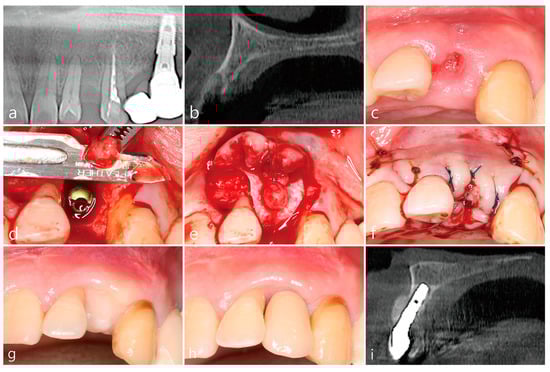

6. Case 4

- A tooth or implant with severe bone loss was removed using extraction forceps under local anesthesia with 2% lidocaine containing 1:100,000 epinephrine;

- A midcrestal incision and two buccal vertical incisions were made. Before raising the flap, special care was taken to ensure a clean dissection of the IGT from the underlying flap without any damage and the IGT is still well-attached to the flap. The IGT was then further separated from the bony housing by using a curette with various curvatures and a periosteal elevator.

- The IGT attached to the buccal flap was dissected to an appropriate thickness using a #15 blade so that the base of the IGT was still attached to the existing flap, and the flap was eventually extended. Periosteal releasing incisions were not performed at the flap base.

- The extraction socket was thoroughly debrided using a Molt curette and a titanium brush.

- A surgical guided stent was used so that the implant (Implantium, Dentium, Suwon, Korea) was placed 2.0 mm subcrestal to the level of the adjacent bone in the extraction socket.

- A synthetic osteoconductive bone graft substitute composed of hydroxyapatite (HA) and beta-Tricalcium phosphate (β-TCP) (Osteon III, Genoss, Suwon, Korea) and a resorbable collagen membrane (Genoss, Suwon, Korea) were placed to cover the implant and the peri-implant osseous defect.

- After covering the bone graft with the collagen membrane, the extended IGT was sutured with the palatal flap with 4-0 Catgut. Next, the buccal flap was closed using 4-0 nylon or black silk.

- Uncovering procedures were performed 4–6 months after initial surgery. Under local anesthesia, the buccal flap was reflected, the regenerated tissue above the implant cover screw was removed, and the healing abutment was connected to the implant. The buccal flap was closed using 4-0 Catgut or black silk. Antibiotics and anti-inflammatory drugs were prescribed for 5 days. The prosthesis was installed 2 months after uncovering.